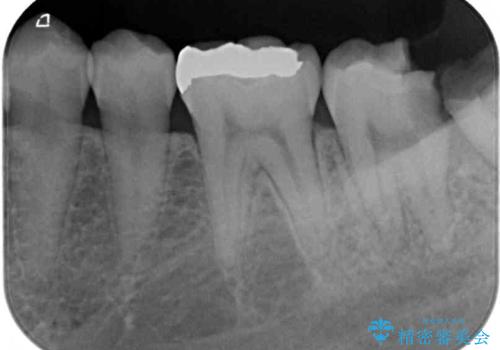

神経組織の失活している歯や歯根だけが残っている歯などがあり、全体的に歯石も多く付着している状態でした。

その後、歯根だけとなっている歯はインプラントに、神経組織の失活している歯は根管治療を行い、いずれもオールセラミッククラウンにて補綴治療を行うこととしました。

右上のインプラント治療は、1DAYインプラント治療(抜歯即時埋入・即時荷重)の適応となりましたので、通常3回必要な外科処置の回数を1回に集約させることができました。